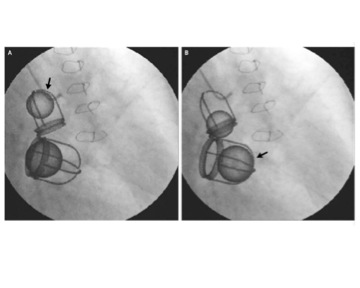

This unique valve can be inserted transfemorally (Retroflex delivery system) or transapically (Ascendra delivery system). Either way, the valve is crimped onto a catheter/balloon device. Under local anesthesia, surgeons use both echocardiographic and fluoroscopic techniques to insert the catheter correctly, which is inserted into the leg (transfemoral) or between the ribs (transpical). Once the catheter reaches the valve of choice, balloon is deployed, expanding and locking the valve in place [17].

This product became commercially available in Europe in 2007. But in the US the valve is undergoing a trial entitled PARTNER (Placement AoRTic TraNscathetER Valve Trial) [1]. This world’s first randomized clinical trial of a transcatheter heart valve started in 2007 and won’t be completed until 2014 [18].

The Edwards SAPIEN transcatheter heart valve comes with implantation-specific risks along with the general risks associated with tissue valves. There are complications with general catheterization through the cardiac system, balloon malfunction, and improperly expanded valves [1].